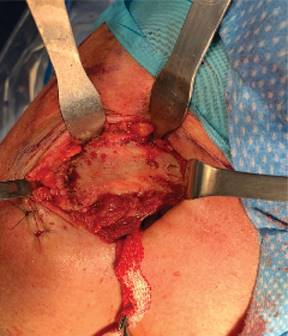

Con el paciente bajo anestesia general balanceada y previa profilaxis antibiótica, se le coloca en posición de silla de playa a 60o de flexión. Por anatomía de superficie se identifican referencias anatómicas: apófisis coracoides, acromion y la articulación AC (Figura 2). Se realiza una incisión en el borde anterior de la clavícula de 5 cm lateral a la articulación AC y se extiende hacia la apófisis coracoides siguiendo las líneas de Langer. Se diseca por planos realizando hemostasia con electrocauterio hasta identificar el músculo deltoides en la parte anterior de la clavícula y la inserción del trapecio en su cara posterior; se realiza disección roma del fascículo deltoideo en dirección a la apófisis coracoides hasta localizar la base de ésta y se pasa una gasa estéril como referencia. Se realiza exposición completa de clavícula y de articulación AC así como de sus tejidos blandos que impiden la reducción articular (Figura 3). Se resecan 3 mm del borde distal de la clavícula y se retiran tejidos blandos (remanente de ligamentos AC y disco articular) (Figura 4).

Figura 3: Se observa exposición del tercio distal de la clavícula y de la articulación acromioclavicular. Con una gasa como referencia de la base de la coracoides.

Figura 4: Se observa resección del borde distal de clavícula y de tejidos blandos que impiden la reducción de articulación acromioclavicular.